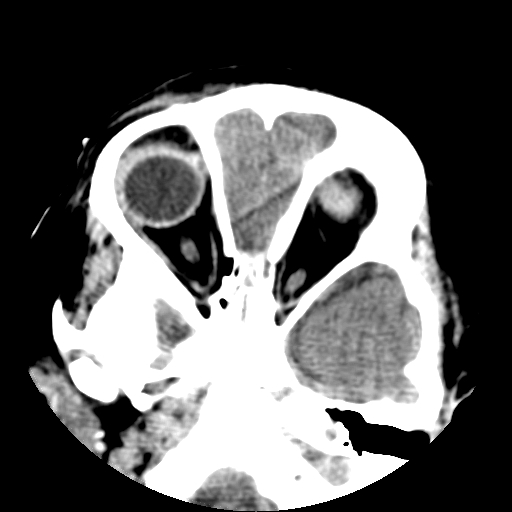

以下是引用深泽交通医院在2009-10-16 8:25:00的发言:[br]右眼环出血伴异物

以下是引用卜一在2009-10-16 15:01:00的发言:[br]右眼球挫裂伤伴异物!

以下是引用拾荒者在2009-10-17 18:38:00的发言:[br]鼻面部皮下积气,右侧睑缘及眼球壁高密度异物影,左侧眼球壁晶状体内侧缘处是圆形低密度影。低密度异物?应提请眼科医生注意。